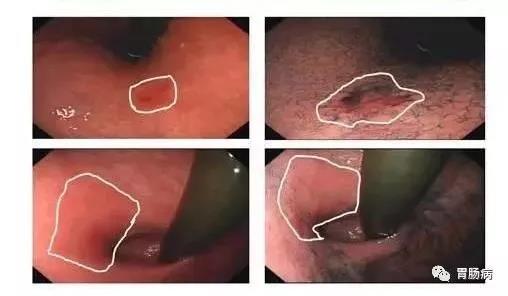

2019年,阿英腹部间断疼痛被诊断为“胃癌”,在中大五院胃肠外科行胃癌根治术,但术中医生意外发现其肝脏有微小转移灶,随即联合肝胆外科行肝脏转移瘤切除术,术后一个月检查发现,肝脏再次出现多发转移瘤。

阿英先接受了6个疗程的靶向联合化疗,肝脏转移瘤明显减少、变小。因患者身体较弱,不适合继续强化疗方案,医生调整了治疗方案,她从第7疗程开始进行靶向药物加口服化疗药物治疗,半年后,她的肝脏转移瘤竟完全消失了。

随后,阿英在医生指导下,规律地进行靶向治疗、小剂量化疗和定期营养支持治疗,至今已有20个月,远远超过晚期胃癌13个月的平均生存期,每三个月一次的复查均显示肝脏肿瘤消失,胃镜检查未见明显异常。